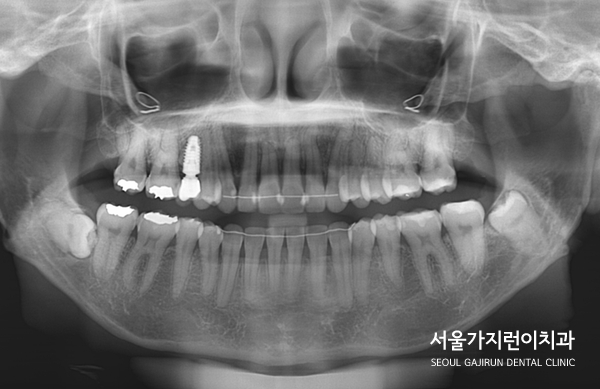

게다가 윗니에 임플란트까지 있는 케이스, 아랫니에는 사랑니도 있었는데요.

교정으로 할 때 임플란트의 존재와 임플란트 주변의 치아이동에 제한이 있다는 점을 염두하고 치아교정 계획을 수립해 진행하기로 했습니다. 또한 설측교정 방식을 적용해 치료를 진행했는데요. 두 개의 와이어로 설측탄댐교정을 진행해 치아이동에 필요한 힘을 안정적으로 주었습니다. 여기에 잇몸에 미니스크류를 식립해 고정원으로 삼고 이동을 시켰는데요.

임플란트한 치아가 움직이지 않도록 최대한 노력했고 다행히 임플란트도 이상 없이 유지되면서 교정을 마칠 수 있었습니다.

말끔하게 해결된 것을 확인할 수 있었습니다. 임플란트도 이상없이 안정적으로 유지된 것을 볼 수 있는데요.

엑스레이 상으로도 중첩되어있던 교합이 정상교합으로 돌아온 것을 확인할 수 있었습니다.